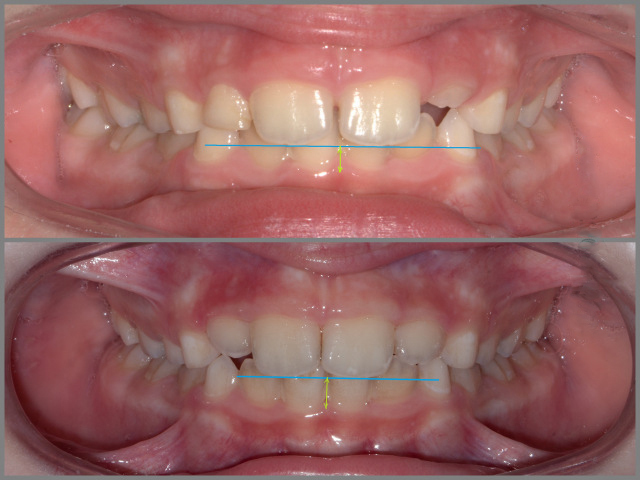

Скобы (Пластинки) для зубов: фото до и после